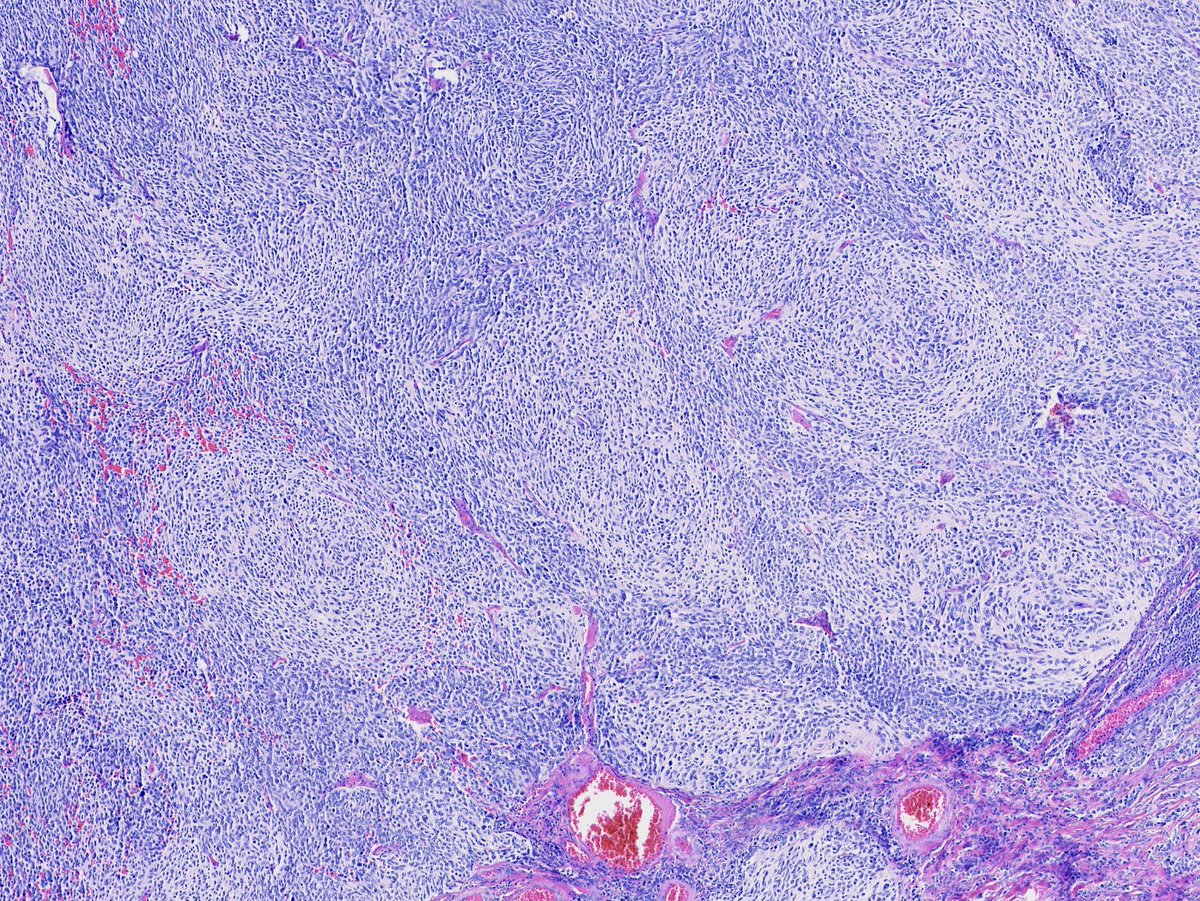

Couldn't be more excited to announce the launch of pathlibrary.com, the virtual slide site I wish had existed during my pathology residency. You can:

- See annotated histologic features